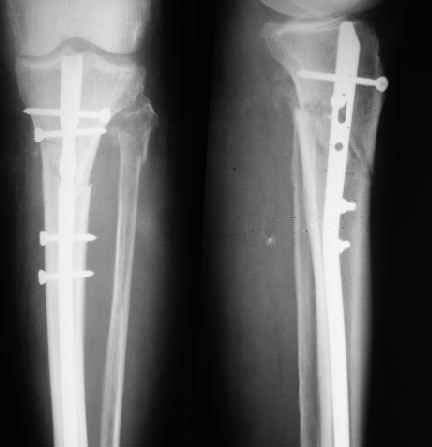

I would be slow to abandon the Ilizarov, especially given your assertion that the pins are intact. The Ilizarov cannot work properly if it does not provide adequate stability. The bone cannot heal if it is kept distracted. I have attached a copy of your radiographs which I modified using Power Point and then saved as a jpeg file.

![]() |

I would add a fourth rod to each of the top and bottom constructs and space the four rods in quadrants. Iwould then place a compression rod medially and a distraction rod laterally. Next I would place hinged rods as shown anteriorly and posteriorly. This will allow correction of the valgus malalignmennt. Once that is accomplished, the four rods in the middle segment can be converted to a straight compression construct to compress the fragments. I would perform these maneuvers in the order described to avoid impingement of the fragments if both compression and angular correction were attempted at the same time.

Please excuse the crude and hurried drawing but I wanted to get an answer off before you burned a bridge by removing the frame and nailing this fracture.